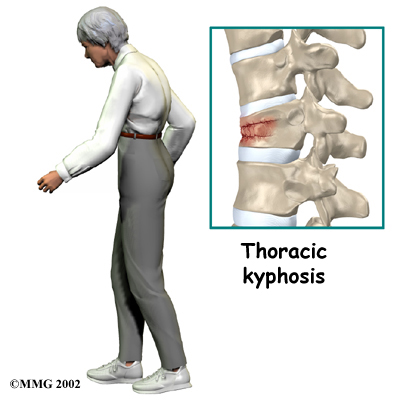

is a disease that weakens bone. Sometimes the bones in the spine weaken to the point that even mild forces can lead to a compression fracture. A simple action like reaching down to pull on a pair of socks can cause a weakened vertebra to fracture. The front of the vertebra (the part closest to the front of the body) crumbles, causing the round vertebral body to become wedge-shaped. This angles the spine forward, producing a hunch-backed appearance, called kyphosis.

Compression fractures caused by thin, weakened bones may cause little or no pain at first. Sometimes pain is centered over the area where the fracture has occurred. The collapsed vertebra gives the spine a hunched appearance, and the loss of vertebral height shortens the muscles on each side of the spine. This forces the back muscles to work harder, causing muscle fatigue and pain. When pain does occur, it usually goes away after a few weeks. However, back pain sometimes escalates to the point that patients seek medical help.

Traumatic compression fractures can produce intense pain in the back that spreads into the legs. If the fracture severely damages the vertebral body, bone fragments may lodge in the spinal canal, pressing on the spinal cord. This can paralyze muscles and impair sensation in the areas supplied by the damaged nerve tissue. Such a fracture may also cause the spine to become unstable. When this happens, the spine eventually tilts forward into increased kyphosis, and the potential grows for future complications with the spinal cord.

Your physical therapist will prescribe exercises for you to do in the clinic and also to be done as part of a home program. Exercises that improve the range of motion in your back, neck, shoulders as well as your hips may be prescribed. If your compression fracture was from osteoporosis, then the extension motion of your upper back (thoracic spine) will be of paramount importance. As mentioned above, wedge compression fractures of the thoracic spine from osteoporosis often lead to a flexed back posture. The risk of losing the ability to function in the upright extended position is high so maintaining this motion is crucial. Even the proper use of your shoulder joints will suffer if the spine loses extension therefore exercises may also be prescribed to maintain shoulder function. Neck range of motion can also be affected if the flexed posturing becomes severe thus range of motion exercises for the neck may also be required. Hip range of motion deficits will be addressed as normal hip range of motion allows the spine to move more freely and decreases the stress on the spinal joints. Patients with traumatic stress fractures don’t often present with the wedge shaped fractures and therefore the primary focus will be the recovery of all ranges of motion, not just thoracic extension.